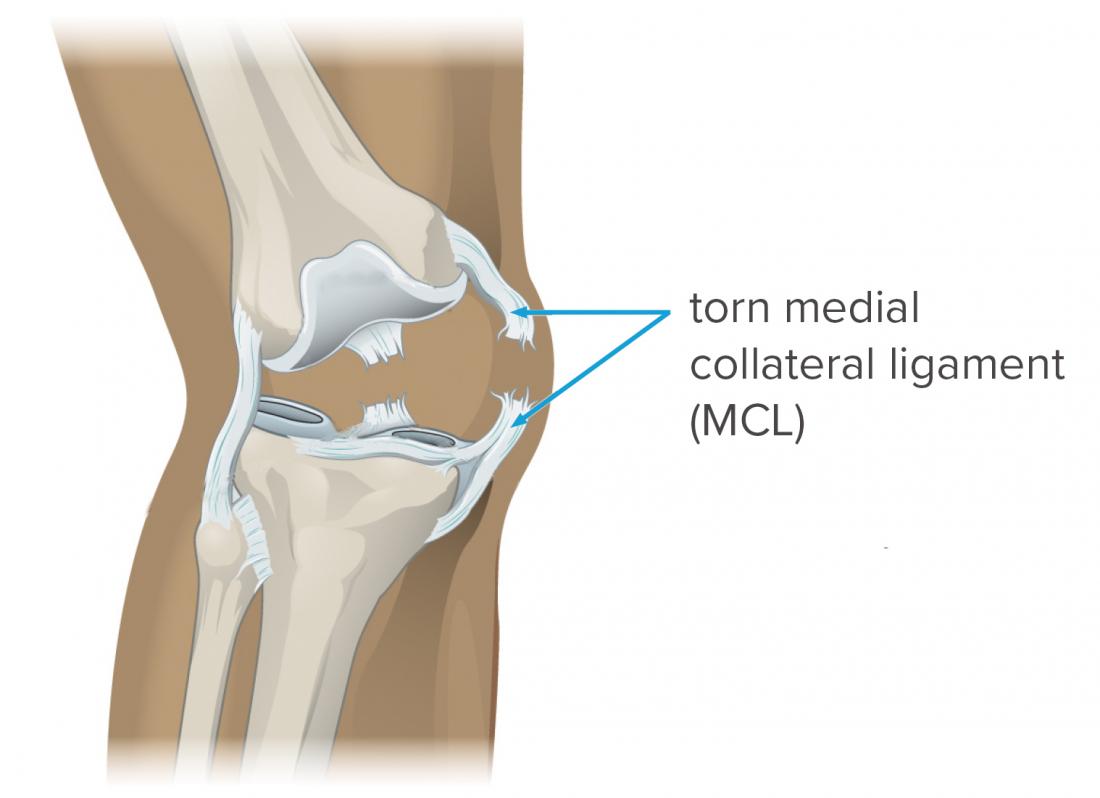

Looking Good Info About How To Repair A Torn Mcl

How to repair a torn mcl. Following your injury, the rice principle is commonly recommended to get the inflammation around the sprained. The surgery to correct a torn knee ligament involves replacing the ligament with a piece of. Van thiel to access the entire.

There are two primary types of mcl surgery: While most mcl injuries can resolve without surgery, there are instances where surgery is the best treatment option. You’ll need to raise your sore knee when you put ice on it, keep weight off the joint, and protect and compress the injury with a knee brace or elastic bandage.

Treatment options for an mcl sprain. The surgery will either repair or reconstruct the mcl. A total rupture of the mcl usually doesn’t require surgery.